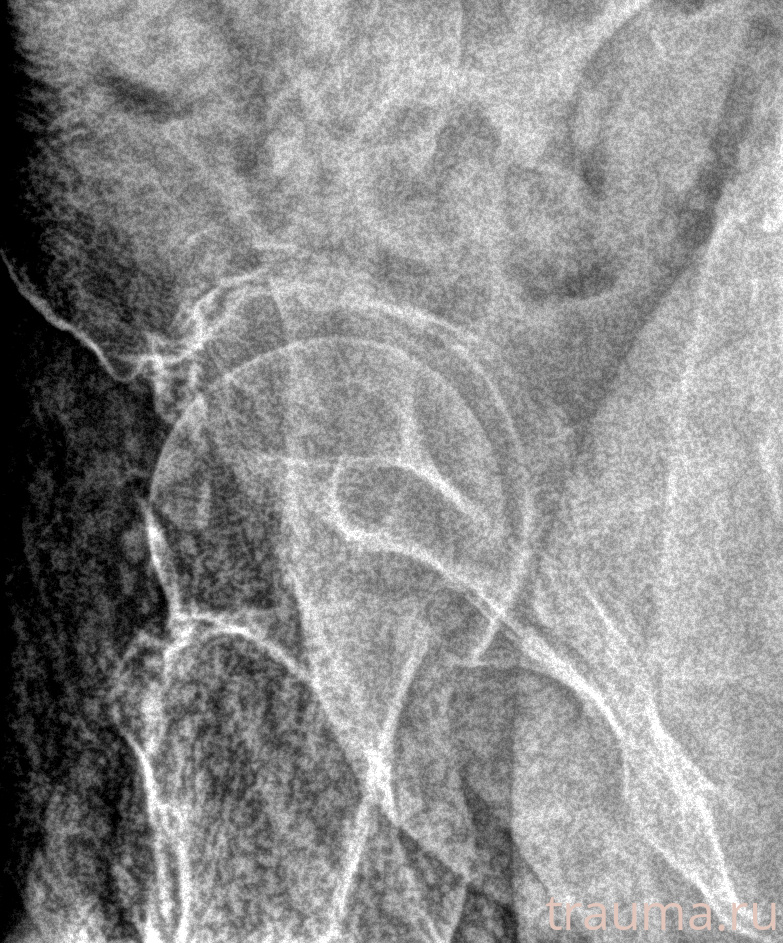

Рентген на дому: по вашему адресу приезжает врач-рентгенолог, травматолог-ортопед с мобильным рентгеновским аппаратом, проводит диагностику травмы или заболевания, делает необходимые рентгенограммы, дает рекомендации по дальнейшему лечению. Получить качественные снимки в домашних условиях возможно благодаря уникальной методике, разработанной МосРентген Центром для института  Склифосовского